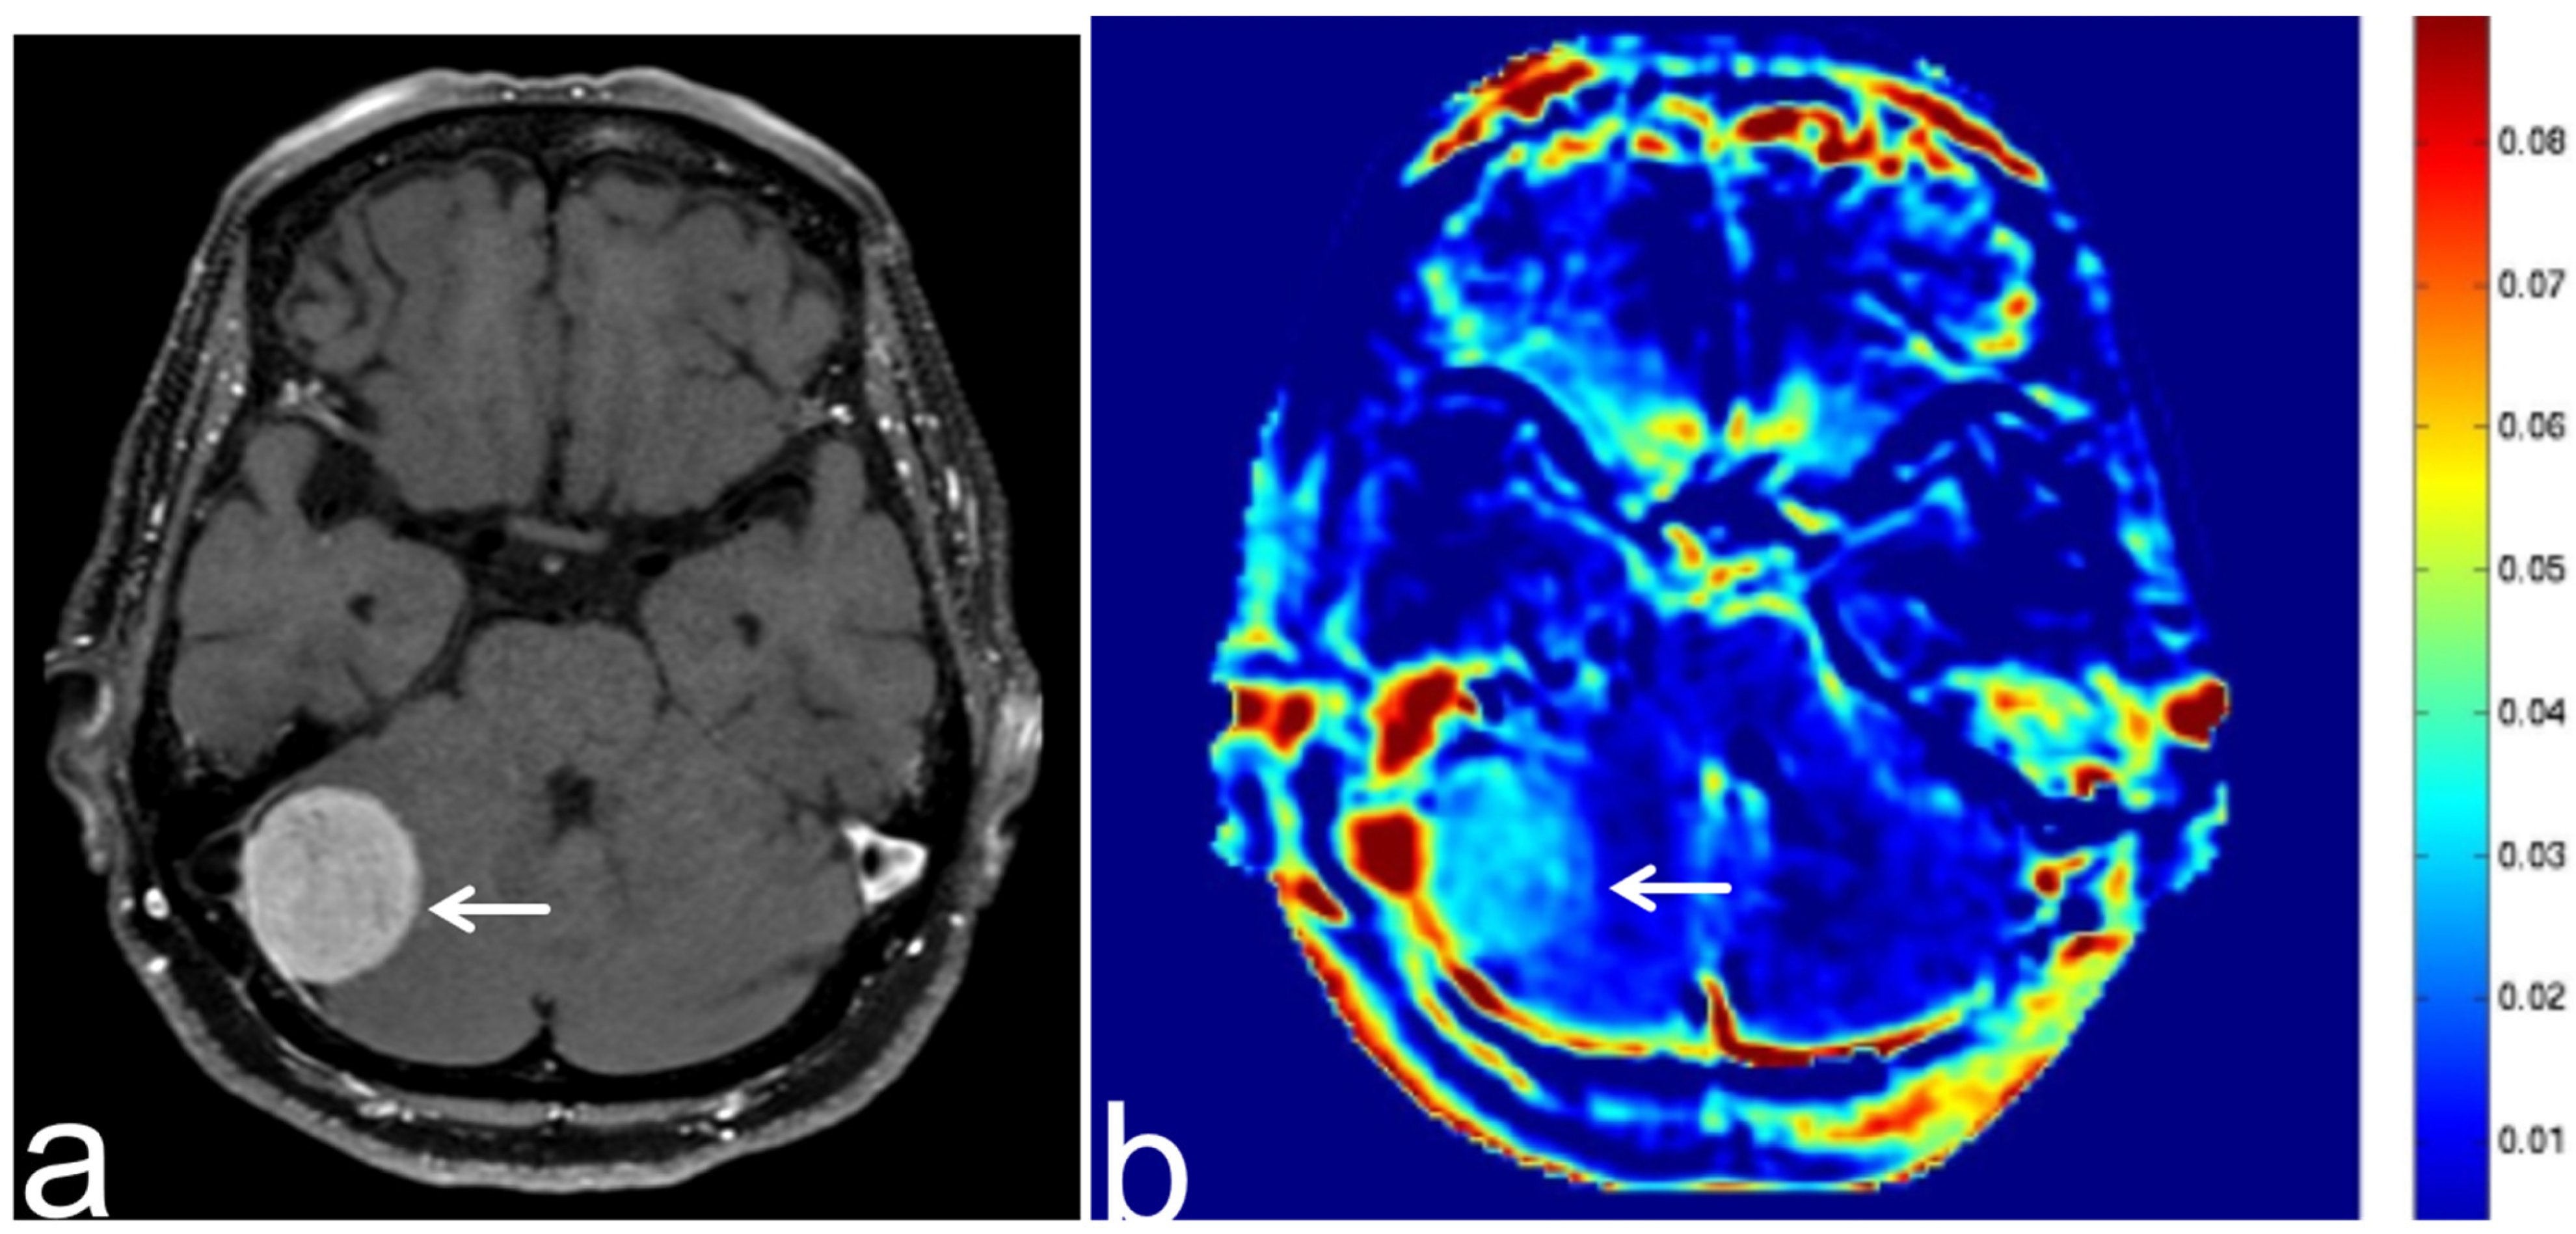

7.3. Schwannoma